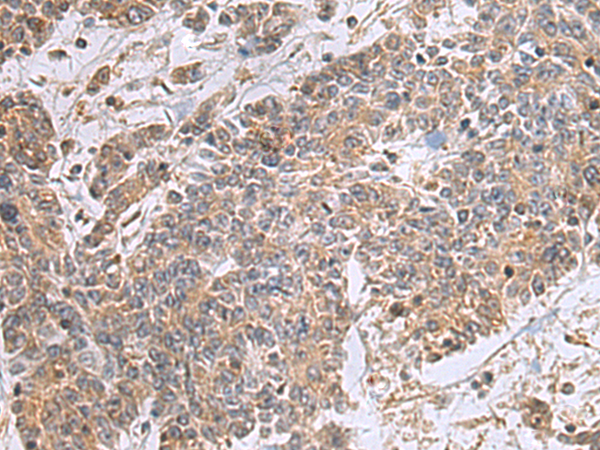

IHC positive control:

Human colorectal cancer and Human esophagus cancer

IHC Recommend dilution:

25-100